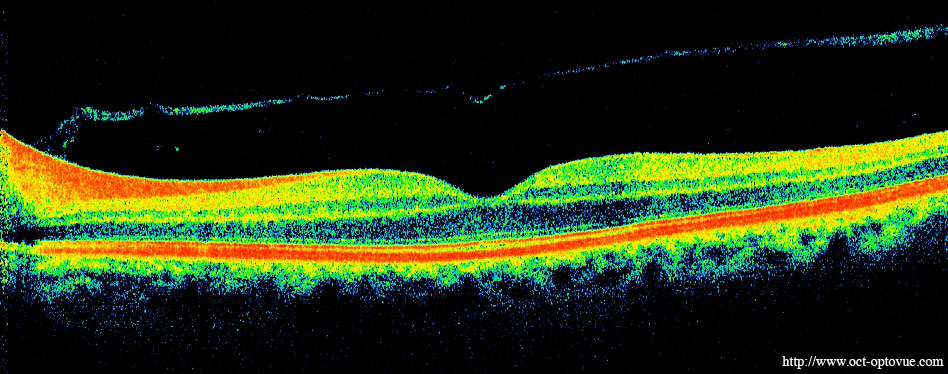

We also use optical coherence tomography (OCT), an imaging technique that uses infrared light reflections off the retina to genrate a cross-sectional view of the retinal tissue. These images can show evidence of AMD and thinning of the retina caused by cell death associated with AMD. This is what an OCT image looks like: